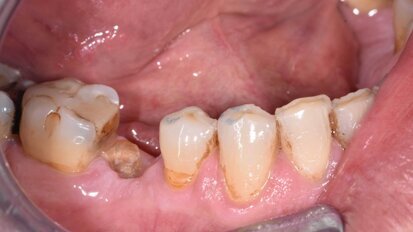

Socket preservation con acido ialuronico reticolato e riabilitazione impianto supportata di un secondo premolare superiore

La paziente si presenta in visita lamentando mobilità e l’insorgenza di un dolore alla masticazione a carico dell’elemento 25. Clinicamente ...